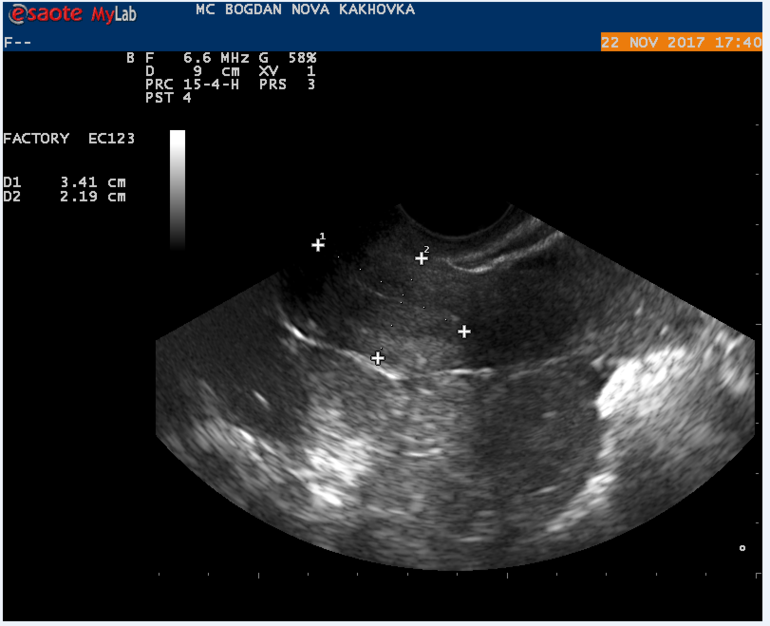

Мой результат УЗИ на 16 ДЦ Кто что может сказать? Тест на О положительный на 13 и 14 ДЦ.

Могли желтое тело не увидеть, а мог и сдуться фоликул, и не было овуляции. А то что эндометрий хороший - еще не показатель, у меня при здутии фолликула и при лютеинизации фолликула он тоже был отличный и соответствовал второй фазе.

Может не увидели жт? Или не успело сформироваться.. Лично не сталкивалась, но читала, что бывает его не видят. Ведь эндик второй фазы у вас.

в протоколе узи не слова о наличии доминантного фолликула, поэтому вряд ли была или будет овуляция в ближайшие дни

судя по узи овуляции не было,доминантного фолликула нет. хотя желтое тело может позже сформироваться